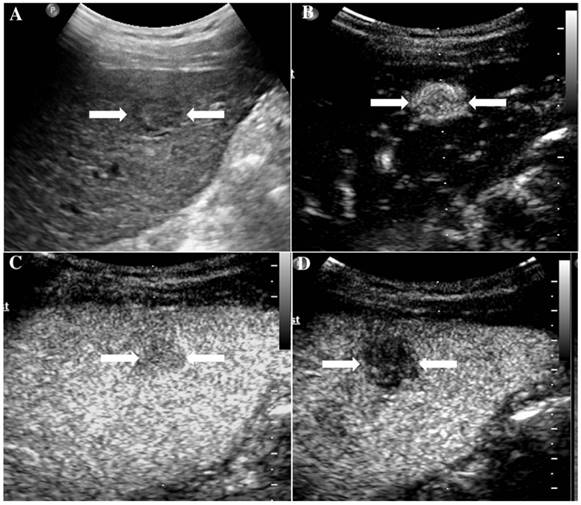

At last, of the 37 observations classified as LR-5, 33 (89.19%) were pathologically confirmed as malignant including 1 ICC (2.7%) and 32 HCC (86.49%). The typical ultrasound images are shown in Figure 1. However, 4 lesions (10.81 %) were histologically proved to be benign, 3 regenerative nodule (8.11%) (Figure 2) and 1 focal nodular hyperplasia (2.7%). With respect to the 8 LR-4 observations, 4 cases (50%) turned out to be HCCs (Figure 3). Angioma, focal nodular hyperplasia (Figure 4) and regenerative nodule accounts for 12.5% (1/8), 12.5% (1/8) and 25% (2/8) respectively. Nine observations categorized as LR-M consist of 7 (77.78%) HCC (Figure 5), 1 (11.11%) ICC and 1 (11.11%) RLH, based on pathological findings. The correct diagnoses of HCC, ICC and benign lesions were used to measure diagnostic accuracy for LI-RADS-CEUS. An example of successful categorization of HCC as LR-3 was shown in Figure 6. For the diagnosis of HCC, the overall diagnostic accuracy of LR-5 was 86.49 % (32/37) and that of LR-4 was 50% (4/8). However, the diagnostic accuracy of LR-M was only 11.11% in the retrospective study (Table 3).

Figure 2

It illustrates an example of misinterpretation with LI-RADS-CEUS (LR-5). The ultimate pathological diagnosis was regenerative nodule (RN). A. Conventional B-mode ultrasound showed a 1.7cm slightly hypoechoic nodule (arrows) on the left hepatic lobe of a 67-year-old woman. B. CEUS showed hyperenhancement (arrows) during the arterial phase. C. CEUS showed hypoenhancement (arrows) during the late phase.